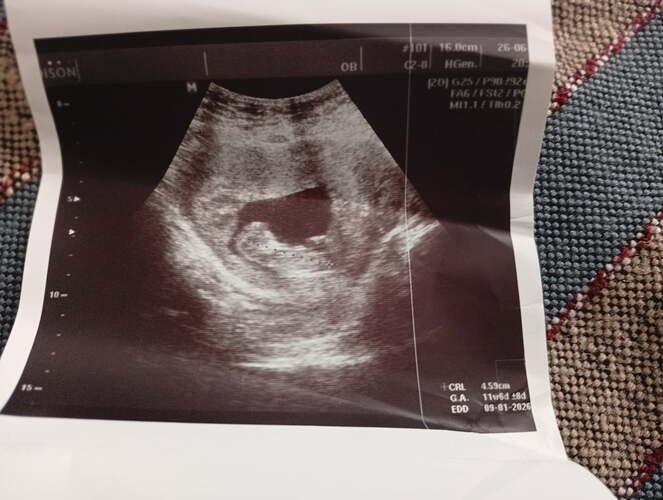

Ben kesenin fotosunu attım gözüküyor mu bilmiyorum sizce cinsiyeti bellimi

Kız gibi duruyor Allah sağlıkla kucağına almayı nasip etsin inşallah ![]()

Kız bu benim tahminim Hayırlı evlat olsun inşallah ![]()

Kız kesesi gibi duruyor sağlıkla gelsin ![]()

Sağlıcakla kucağına al canım. Bence erkek.

erkek gibi, sağlıkla gelsin bebişiniz.